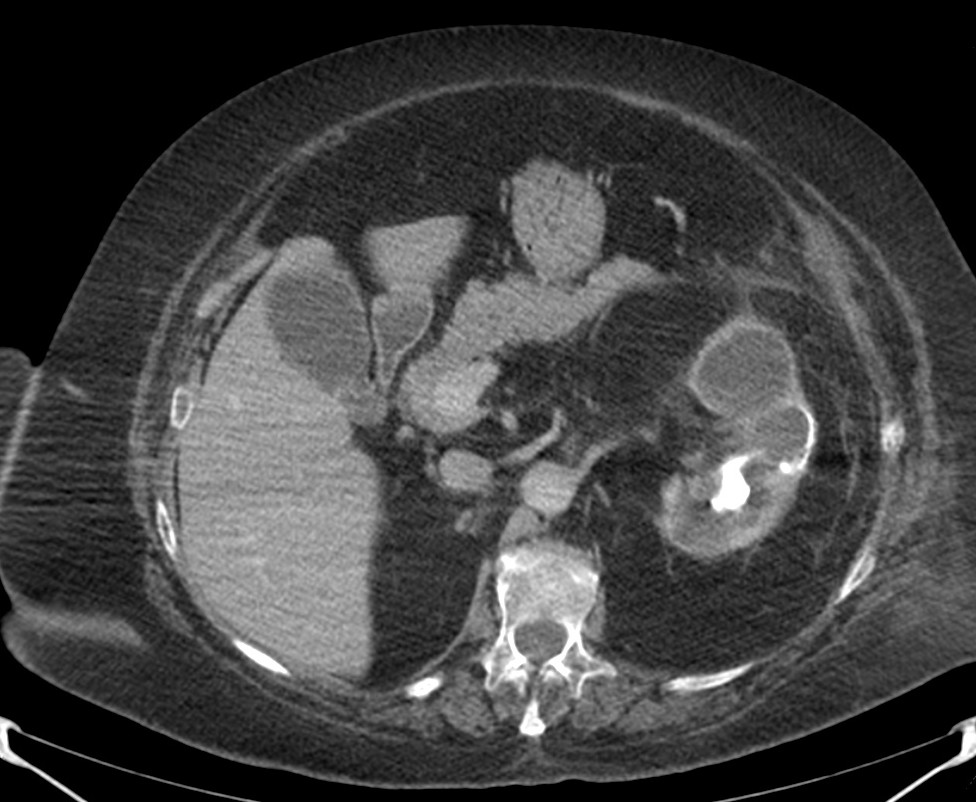

Paciente mujer de 62 años que acude por decaimiento general con fiebre y dolor en flanco izquierdo. Ingresa en UVI por signos de sepsis

Nos cuenta antecedentes de pielonefritis e hidronefrosis crónica.

Hallazgos en imagen:

Estos hallazgos pueden ser dificiles de interpretar, ya que una paciente con hidronefrosis crónica y litiasis en el uréter puede haber sufrido una obstrucción que origina un cuadro de dolor en FRI con ruptura de cálices y colección extra axial. Otra probabilidad puede ser un angiomiolipoma que ha roto un aneurisma y ha producido un sangrado. También podríamos estar ante una pionefrosis aunque dada dada la clínica, los antecedentes y al observar los hallazgos en TC podríamos establecer la sospecha de pielonefritis xantunogranulomatosa con alta probabilidad. La confrimación vendrá dada con la nefrostomía y estudio de anatomía patológica.